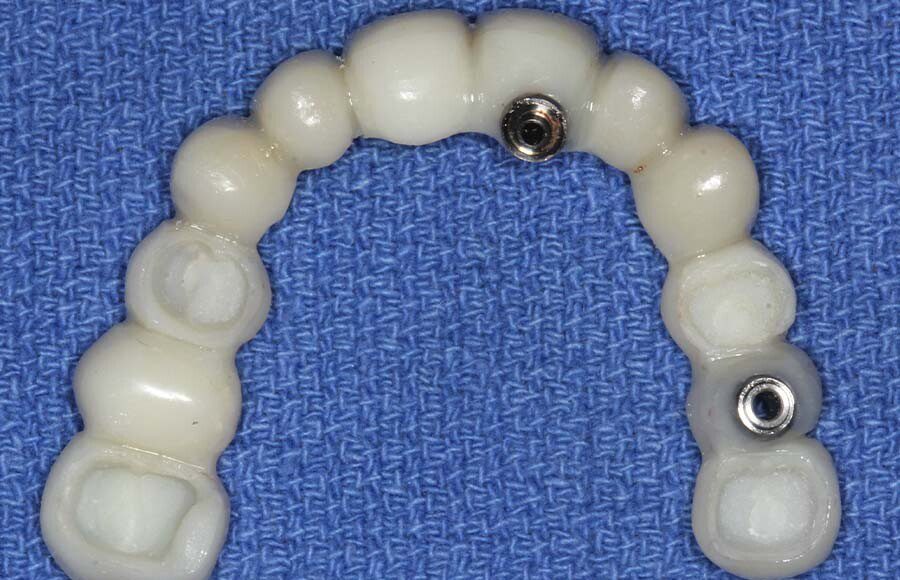

Smile GalleryImplant RestorationsFull Mouth Implant Restoration Full arch zirconia implant bridge (full smile) 1 of 37 Pre-op full smile Pre-op lips retracted Pre-op panoramic x-ray Extraction of strategic teeth Placement of implants Extraction of some remaining teeth after verification of adequate implant stability Occlusal view Post-op panoramic x-ray Immediately fabricated provisional restoration (tissue side view) Immediately fabricated provisional restoration (occlusal side view) Immediate provisional delivered on day of surgery Immediate provisional 2 weeks later Scalloped tissue developed from the provisional at 2 weeks Jig used for making a master impression Provisional in place (full smile) Provisional in place (lips retracted) Provisional in place (right side) Provisional in place (left side) Wax try-in (full smile) Wax try-in (right side full smile) Wax try-in (left side full smile) Wax try-in (full face, lips together) Wax try-in (full smile) Wax try-in (right side) Wax try-in (left side) Wax try-in (lips retracted) Full arch zirconia implant bridge on master cast (frontal view) Full arch zirconia implant bridge on master cast (occlusal view) Implant positions and soft tissue representation on master cast (occlusal view) Soft tissue representation on master cast (frontal view) Full arch zirconia implant bridge (tissue side view) Soft tissues on day of delivery (occlusal view) Soft tissues on day of delivery (frontal view) Full arch zirconia implant bridge delivered (lips retracted) Full arch zirconia implant bridge (lips retracted, close up) Post treatment panoramic x-ray Full arch zirconia implant bridge (full smile)